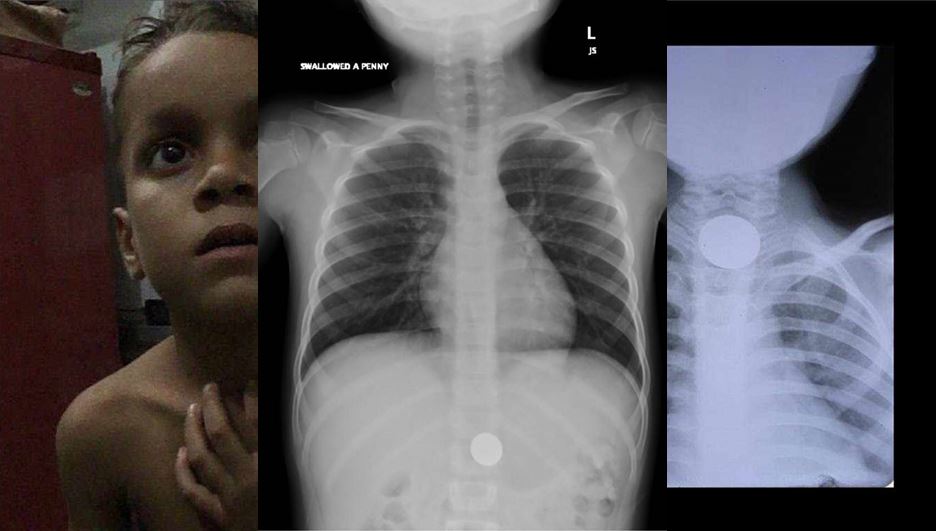

ثالثا:أغلب الإصابات تتراوح من ٦ اشهر- ٤ سنوات..

وهنا صور لابتلاع البطاريات الخطيرة جدا...